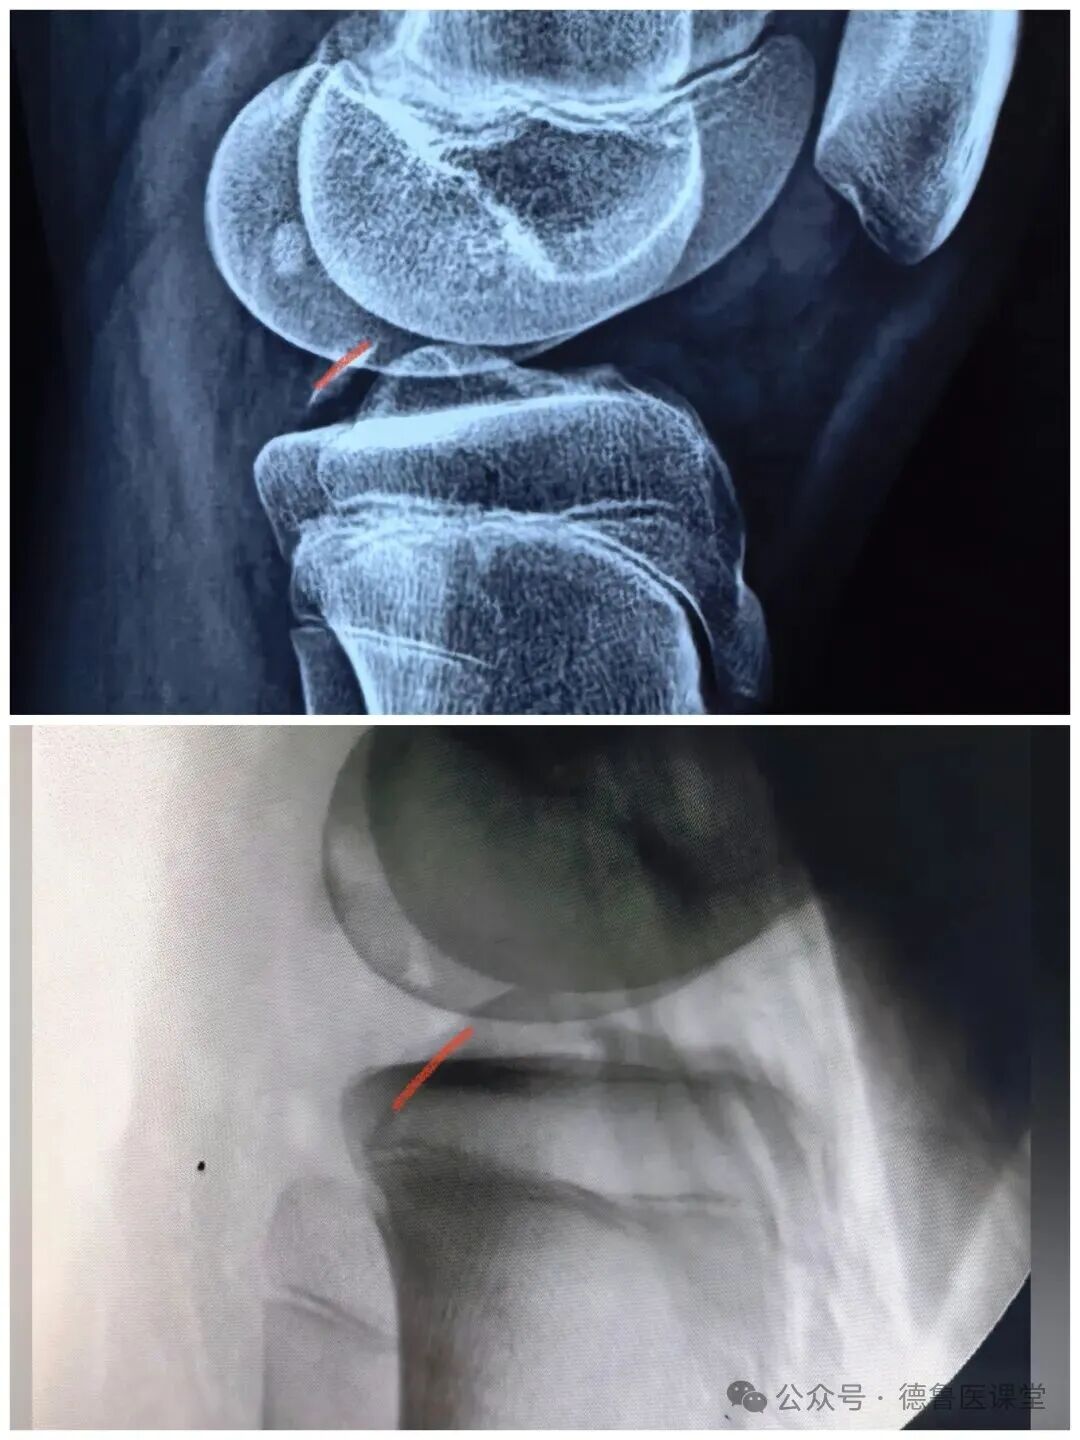

后叉止点撕脱骨折

Ⅲ型 完全移位

儿童骨科,建议手术

运动医学科,建议手术

创伤骨科,建议手术